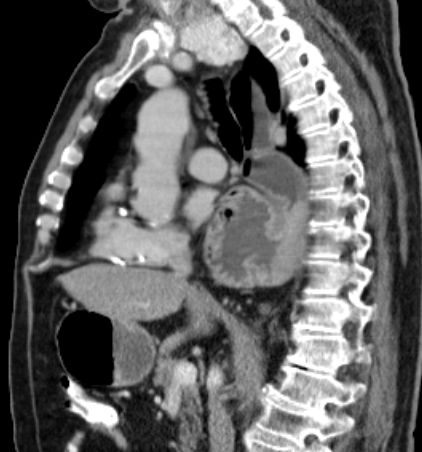

Hiatus - Hernie 83-jähriger Patient, der seit 2 Wochen Schluckbeschwerden mit unmittelbarem Erbrechen nach Nahrungsaufnahme hat. Das CT zeigt eine breite Zwerchfellhernie mit Teilen des Magens.

Die hintere Wand des intrathorakalen Magens ist verdickt: Adenokarzinom.

Der Ösophagus ist dilatiert und distal wandverdickt.

Adenokarzinom unter Magenschleimhaut.

Adenokarzinom unter dem Plattenepithel des Ösophagus.